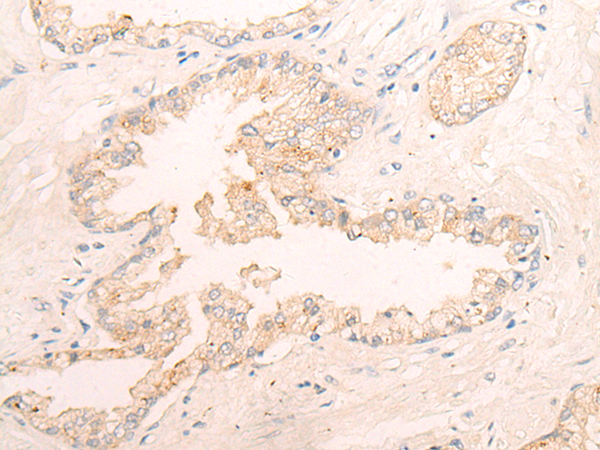

The image is immunohistochemistry of paraffin-embedded Human thyroid cancer tissue using 47101(ELANE Antibody) at dilution 1/25. (Original magnification: ?00)